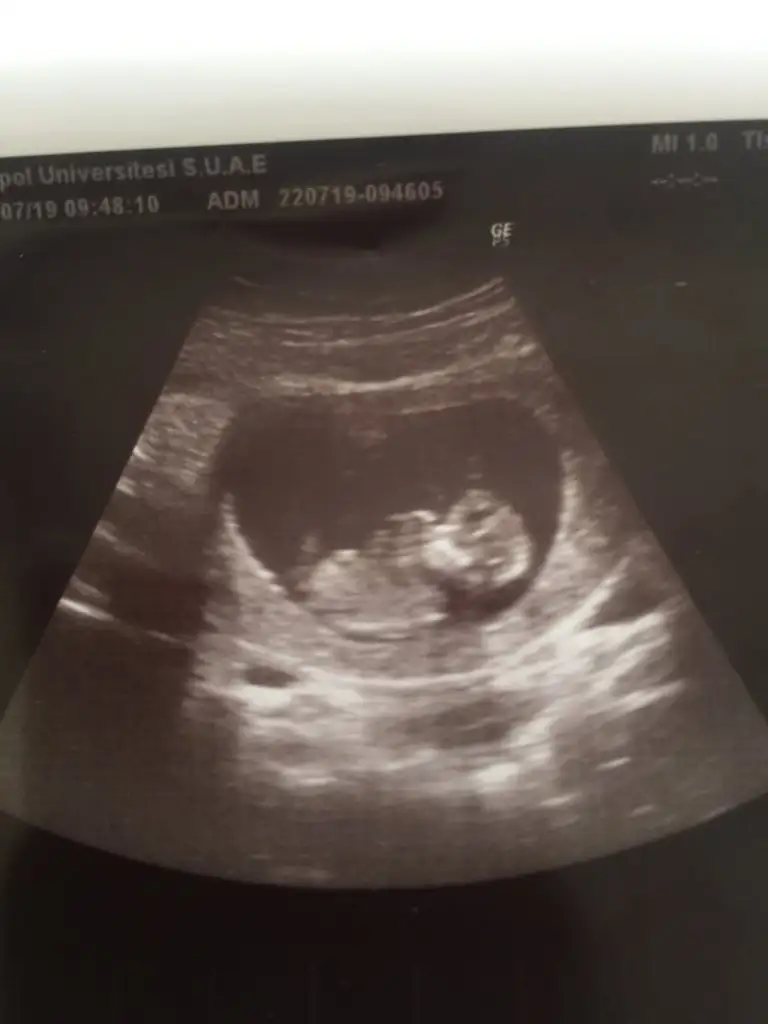

Slm banada yardımcı olurmusunuz dr net bişey demedi daha çok kafam karıstı... Ikra meyra Ikra meyra

Eklentiler

• 393E3389-6DE6-4C3A-A60C-5746D021AC42.webp

393E3389-6DE6-4C3A-A60C-5746D021AC42.webp

47,2 KB · Görüntüleme: 46

• D76DFD14-0C40-41DB-BF96-ADFF757E41E0.webp

D76DFD14-0C40-41DB-BF96-ADFF757E41E0.webp

17,5 KB · Görüntüleme: 44

• BCE73113-D1C3-4061-82ED-6BF9BE6AEC43.webp

BCE73113-D1C3-4061-82ED-6BF9BE6AEC43.webp

17 KB · Görüntüleme: 48

Doktorumuz soylemiyor kimseye 16 dan once. Hayirlisi bakalim. Bir kizim var zaten ilk once saglikli olmasini diliyorum Rabbimden